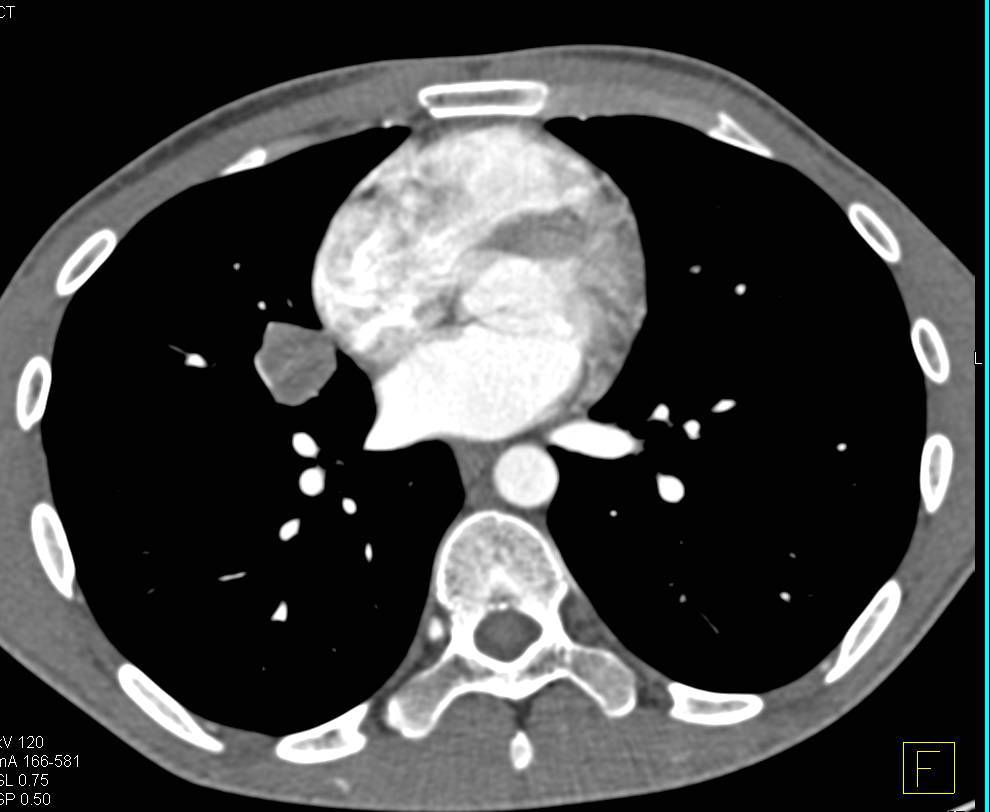

Metastatic GIST Tumor to the Liver Best Seen on Venous Phase Images